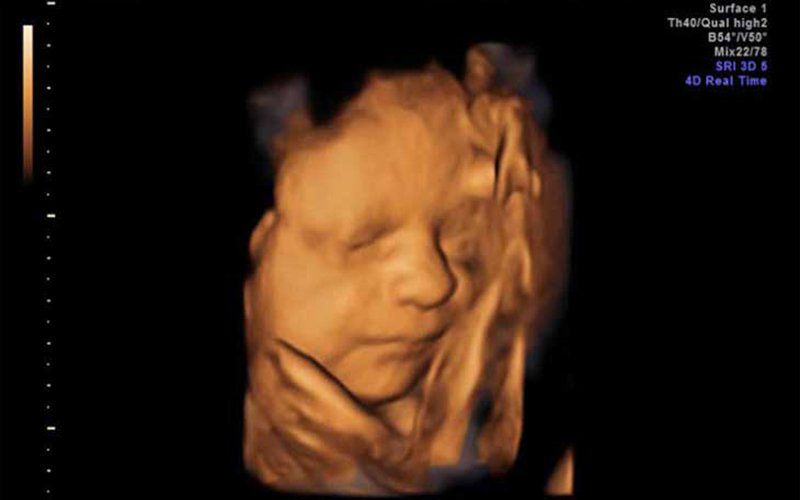

hơn hết là đã nhìn gần rõ mặt rồi ☺️

giống bố quá

70% là con trai rồi